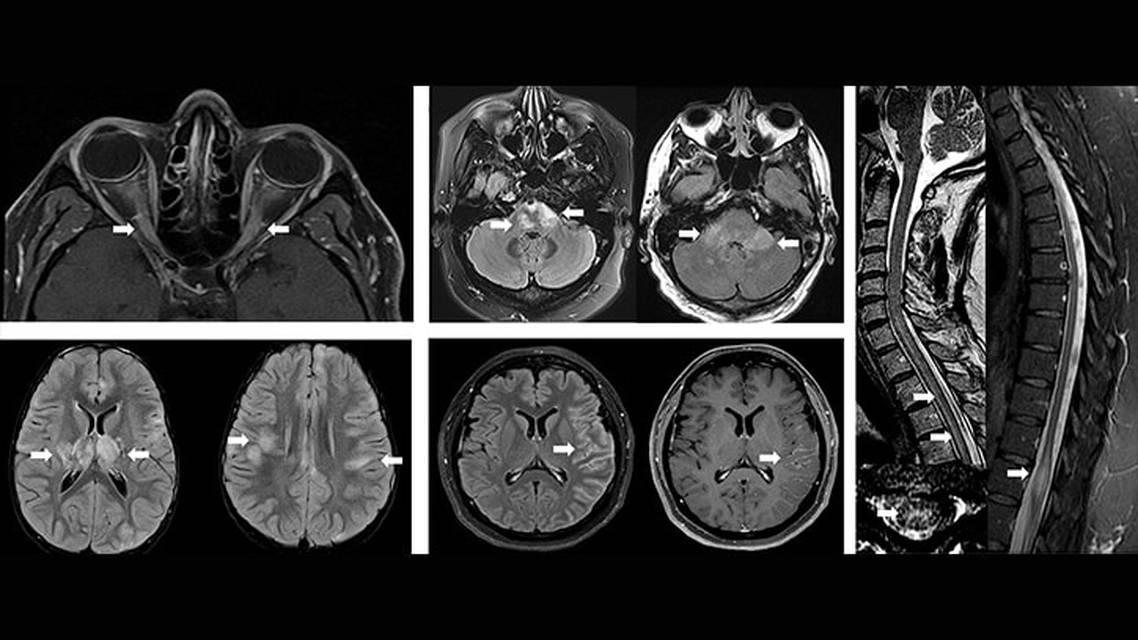

MRI of the orbits during acute optic neuritis typically shows a longitudinally extensive optic nerve T2 hyperintensity and enhancement (involving >50% of the optic nerve length) (Figure), sometimes with perineural optic nerve enhancement, a finding particularly suggestive of MOGAD. The anterior segment of the optic nerve is typically affected, and involvement of the optic chiasm is rare. Most individuals have good recovery of vision despite severe impairment at presentation.7

In children, ADEM (or ADEM-like) is the most common or second most common (depending on series) clinical manifestation of MOGAD. MOG-IgG is found in almost half of the children presenting with ADEM.8 ADEM can also occur in adults, although it is rare.3,5 Brain MRI typically reveals poorly demarcated T2-hyperintense lesions involving the white matter and deep gray matter3,5,8 (Figure).

Spinal cord MRI often shows longitudinally extensive transverse myelitis (T2 lesion extending contiguously over at least 3 vertebral segments), although it can also be short segment. Axial T2 sequences can show an “H sign” with hyperintensity of the gray matter (Figure). Gadolinium enhancement is present in half of the cases, and it is typically faint and patchy. There is predilection for conus medullaris involvement, and sometimes enhancement can extend to the cauda equina roots.9

Brainstem or cerebellar syndromes may also occur in about one-third of individuals with MOGAD, typically in combination with involvement of other regions. Brain MRI usually shows poorly demarcated and large lesions, often with lesions in the pons and involving the middle cerebellar peduncles10 (Figure).